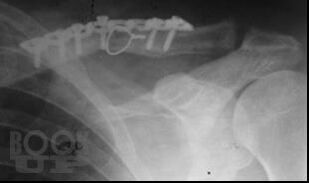

Переломы средней трети ключицы

Учебное пособие содержит основные принципы диагностики и лечения пациентов с повреждениями ключицы с использованием современных технологий, включает тесты, ситуационные задачи. Является дополнением к учебнику «Травматология и ортопедия». Иллюстрации и рисунки взяты из сети интернет в открытом доступе.

Предназначено для студентов, обучающихся по специальности 31.01.05 Лечебное дело. Учебное пособие содержит основные принципы диагностики и лечения пациентов с переломами ключицы с использованием современных технологий, включает тесты, ситуационные задачи.